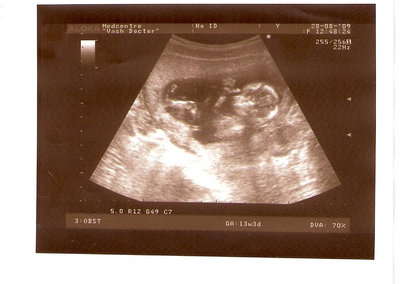

СЫН

| Вложения: |

2.jpg [ 110.14 КБ | Просмотров: 2631 ]

13 НЕД И 5 ДНЕЙ

3.jpg [ 96.81 КБ | Просмотров: 2629 ]

Nikisa писал(а): Foto prosto chudesnoe. A na kakom sroke uznali, chto sin.............. НА 13 НЕДЕЛЯХ.КАК РАЗ ВОТ В ЭТО узи, ОНО УМЕНЯ ВТОРОЕ БЫЛО. ЭТО КОНЕЧНО МАЛЕНЬКИЙ СРОК ДЛЯ ОПРЕДЕЛЕНИЯ ПОЛА. НО Я ПОПРОСИЛА ВРАЧА(ЭТО КТСТАТИВ РОССИИ БЫЛО) ХОТЯ БЫ ПРЕДПОЛОЖИТЬ. ЕЙ ВСЁ ТАКИ УДАЛОСЬ РАССМОТРЕТЬ.НУ ВООБЩЕМ ЧЕРЕЗ НЕСКОЛЬ ДНЕЙ ПОЙДУ К ВРАЧУ, УЖЕ АМЕРЕКАНСКОМУ И УЗНАЮ ТОЧНО. К ТОМУ ВРЕМЕНИ У МЕНЯ БУДЕТ СРОК 18 НЕДЕЛЬ. ХОТЕЛОСЬ БЫ ПОСМОТРЕТЬ НА ДРУГИЕ ФОТО НА ЭТОМ СРОКЕ ИЛИ БОЛЬШЕ. ТАК ЧТО ВЫКЛАДЫВАЙТЕ, ЕСЛИ НЕ ЖАЛКО!